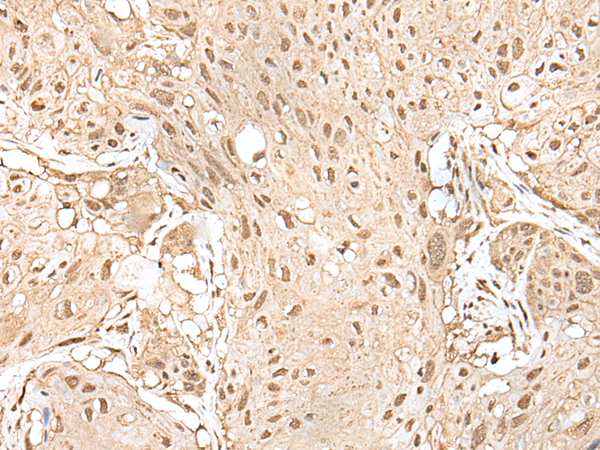

IHC positive control: |

Human esophagus cancer and human brain |

IHC Recommend dilution: |

25-100 |